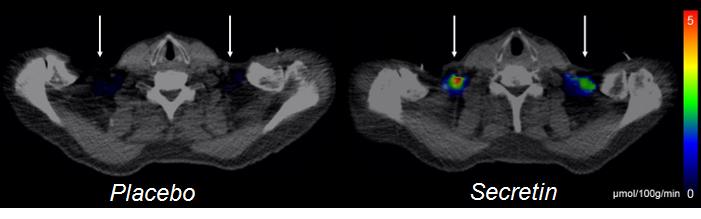

- Secretin is a hormone secreted into blood circulation by the intestines, and it stimulates the production of peptic juices in the pancreas when we have meals. In our research, we discovered secretin receptors in the brown adipose tissue of healthy people, which suggested that secretin also affects brown fat. Secretin infusions not only increased glucose uptake in brown adipose tissue, but also elevated energy expenditure in the whole body, says Doctoral Candidate, Cardiologist Sanna Laurila from the University of Turku.

Using magnetic resonance imaging, the researchers discovered that secretin also decreased the activity of the reward system in the brain when the subjects were looking at delicious photos of food. The subjects' decreased appetite could also be verified with a questionnaire survey, and the time between their meals grew by 40 minutes.